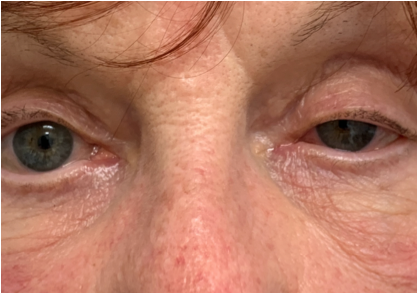

Case Challenge 15 – March 2021

Read more: Case Challenge 15 – March 2021A 73-year-old woman presented urgently with a sudden left ptosis. She noticed it immediately after undergoing parathyroid surgery to remove 3 adenomas the day before. At first, she and her family thought it might have been due to the surgical anesthesia,